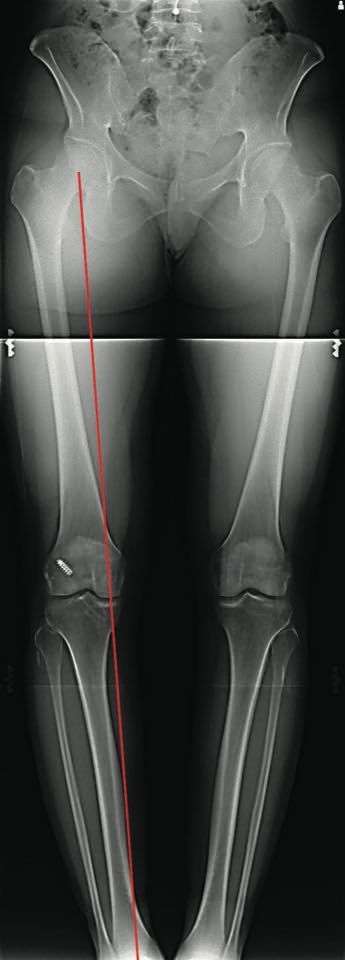

Actualité Gestion des tunnels osseux pour les reconstructions itératives du LCA Quelle stratégie ? , Andy Williams Fortius Clinic, Londres, Angleterre N°256 Cahier 1 - Août/Septembre 2016 ● 14 min de lecture